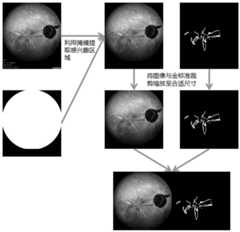

| CN109166126B (en) | Method for segmenting paint cracks on ICGA image based on condition generation type countermeasure network | |